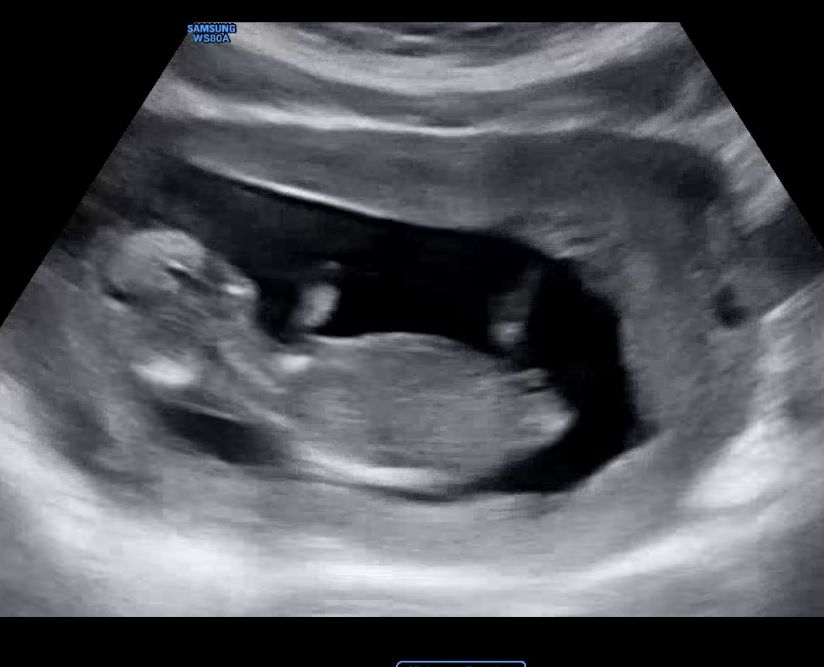

12주 3일차 성별 남아일까요? 여아일까요?

고수님들 ♥ 부탁드려요♥